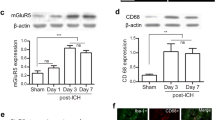

Irisin treatment inhibited microglia/macrophage activation, neutrophil infiltration, and the expression of IL-1β at 24 h after ICH

At 24 h post-ICH, the levels of Iba-1 and MPO in the perihematomal area were performed by immunofluorescence staining to detect microglia/macrophage activation and neutrophil infiltration. Immunofluorescence staining showed that the numbers of Iba-1, IL-1β, and MPO-positive cells were significantly increased in ICH + vehicle group when compared with the sham group (p < 0.001, Fig. 5A–D). However, irisin post-treatment significantly reduced the number of Iba-1 (p < 0.05, Fig. 5A, B), MPO (p < 0.01, Fig. 5A, C), or IL-1β-positive cells (p < 0.01, Fig. 5A, D) in the perihematomal area than that in ICH + vehicle group. In addition, western blot results showed that the expression of Iba-1, MPO, and IL-1β in the ipsilateral hemisphere were significantly decreased with irisin post-treatment when compared with ICH + vehicle group at 24 h after ICH (p < 0.05, Fig. 5E–G).

Effects of irisin on microglia/macrophage activation and neutrophil infiltration after ICH. A Representative images of immunofluorescence staining of Iba-1 (green), MPO (green), and IL-1β (green) in the perihematomal area at 24 h after ICH. B–D Quantitative analyses of Iba-1, MPO, and IL-1β-positive cells in the perihematomal area at 24 h after ICH, n = 6 per group. E–G Representative Western blot bands and quantitative analyses of Iba-1, MPO, and IL-1β protein levels in the ipsilateral hemisphere at 24 h after ICH. *p < 0.05, **p < 0.01, ***p < 0.001 vs. sham group; #p < 0.05, ##p < 0.01 vs. ICH + vehicle group. Error bars are represented as mean ± SD. One-way ANOVA, Tukey’s test, n = 6 per group, scale bar = 50 μm

Irisin treatment increases the phenotypic switch of microglia/macrophage from pro-inflammatory to an anti-inflammatory phenotype

In response to acute brain injury, microglia become activated and develop classic pro-inflammatory (M1) or anti-inflammatory (M2) phenotypes. The different phenotypes of microglia influence the outcome of ICH. We performed immunofluorescence staining to confirm whether irisin affects microglia/macrophage phenotypic switch. The numbers of the Iba-1+ microglia were significantly reduced in the perihematomal area of the ICH + irisin group compared with the ICH + vehicle group (p < 0.05, Fig. 6A–C), which suggested that irisin alleviated microglial activation at 72 h post-ICH. Comparing with the ICH + vehicle group, we found that irisin post-treatment significantly decreased the number of Iba1+CD16+ M1 microglia/macrophages (p < 0.01, Fig. 6D) and significantly increased the numbers of Iba1+CD206+ M2 microglia/macrophages (p < 0.01, Fig. 6E) in the perihematomal area at 72 h post-ICH. To further investigate the phenotype characteristics of microglia/macrophages, qPCR was conducted to evaluate the mRNA expression levels of M1 phenotype markers (CD16, CD32, IL-1β, iNOS, IL-6, and CD11b) and M2 phenotype markers (CD206, Arg1, CCL22, TGF-β, IL-13, and YM1/2). Compared with the vehicle group, mice treated with irisin showed lower expression of M1 markers (CD16, CD32, and IL-1β) and higher expression of M2 markers (CD206 and CCL22) in the perihematomal region (p < 0.05, Fig. 6F, G). Taken together, these findings showed that irisin post-treatment increased the phenotypic switch of microglia/macrophages from pro-inflammatory to anti-inflammatory phenotype after ICH.

Irisin promotes the phenotype of microglia/macrophage from pro-inflammatory into anti-inflammatory at 72 h post-ICH. A Representative double immunofluorescence staining for Iba1 (green) and CD16 (red) in the perihematomal area. Scale bar = 50 μm. B Representative images of Iba1 (green) and CD206 (red) immunostaining in the perihematomal area. Scale bar = 50 μm. C–E Quantitative analyses of Iba1+ microglia/macrophage, Iba1+/CD16+ M1 microglia/macrophage and Iba1+/CD206+ M2 microglia/macrophage in the perihematomal area at 72 h after ICH. F M1-associated mRNA levels were evaluated including CD16, CD32, IL-1β, iNOS, IL-6, and CD11b. G M2-associated mRNA levels were evaluated including CD206, Arg1, CCL22, TGF-β, IL-13, and YM1/2. Data were represented as mean ± SD. *p < 0.05, **p < 0.01, ***p < 0.001 vs. sham group; #p < 0.05, ##p < 0.01 vs. ICH + vehicle group. One-way ANOVA, Tukey test, n = 6/group